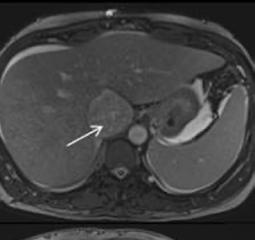

Creative Director

Tim Uden

Design Manager

Stacey White

Senior Designers

Owen Silcox

Tamara Kondolomo

Creative Artworker

Dillon Benn Grove

Designers

Shanjok Gurung, Fabio van Paris

Junior Designer

Helena Spicer